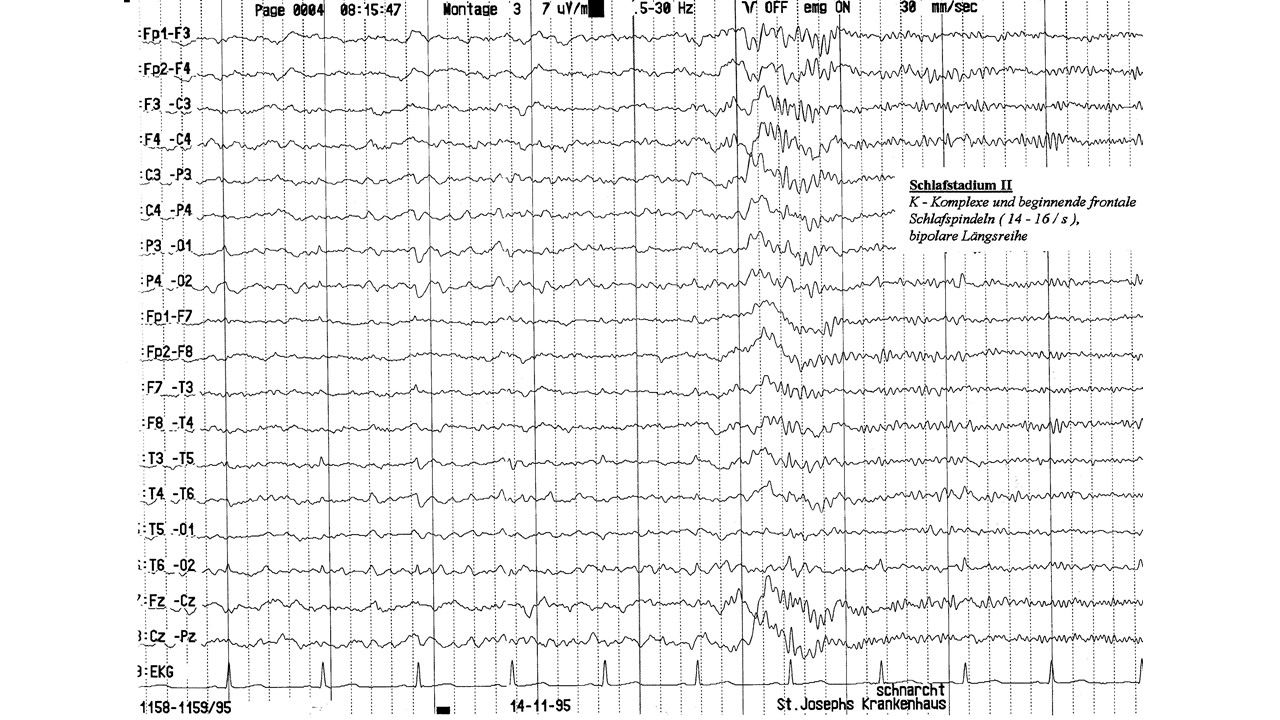

folie95.jpg